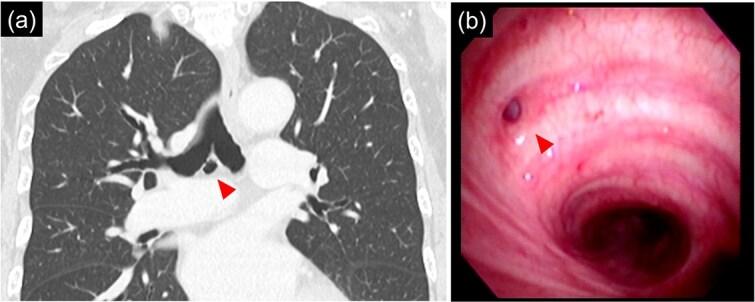

A tracheobronchial diverticulum is an incidental airway abnormality often identified on chest computed tomography. Thoracic surgery involves manipulation around the bronchial diverticulum, assessing its presence, and implementing appropriate strategies to prevent injury. However, few reports document cases of thoracic surgery complicated by a bronchial diverticulum. Herein, we report a case of surgical resection of lung cancer with a bronchial diverticulum. A 66 year-old woman was diagnosed with right lower lobe lung cancer, c-T1b N1 M0 stage IIB right lower-lobe lung cancer. Chest computed tomography showed a 9 mm bronchial diverticulum below the carina. Surgical intervention for bronchial diverticulum was performed simultaneously with the dissection of the inferior mediastinal lymph nodes. Right lower lobectomy with lymph node resection was safely performed using robot-assisted surgery.

气管支气管憩室是一种常在胸部计算机断层扫描中偶然发现的气道异常。胸外科手术涉及在支气管憩室周围进行操作,评估其存在情况,并实施适当策略以防止损伤。然而,很少有报告记录胸外科手术并发支气管憩室的病例。在此,我们报告一例伴有支气管憩室的肺癌手术切除病例。一名66岁女性被诊断为右下叶肺癌,c-T1b N1 M0 ⅡB期右下叶肺癌。胸部计算机断层扫描显示隆突下方有一个9毫米的支气管憩室。在清扫纵隔下淋巴结的同时对支气管憩室进行了手术干预。使用机器人辅助手术安全地进行了右下叶切除及淋巴结切除术。